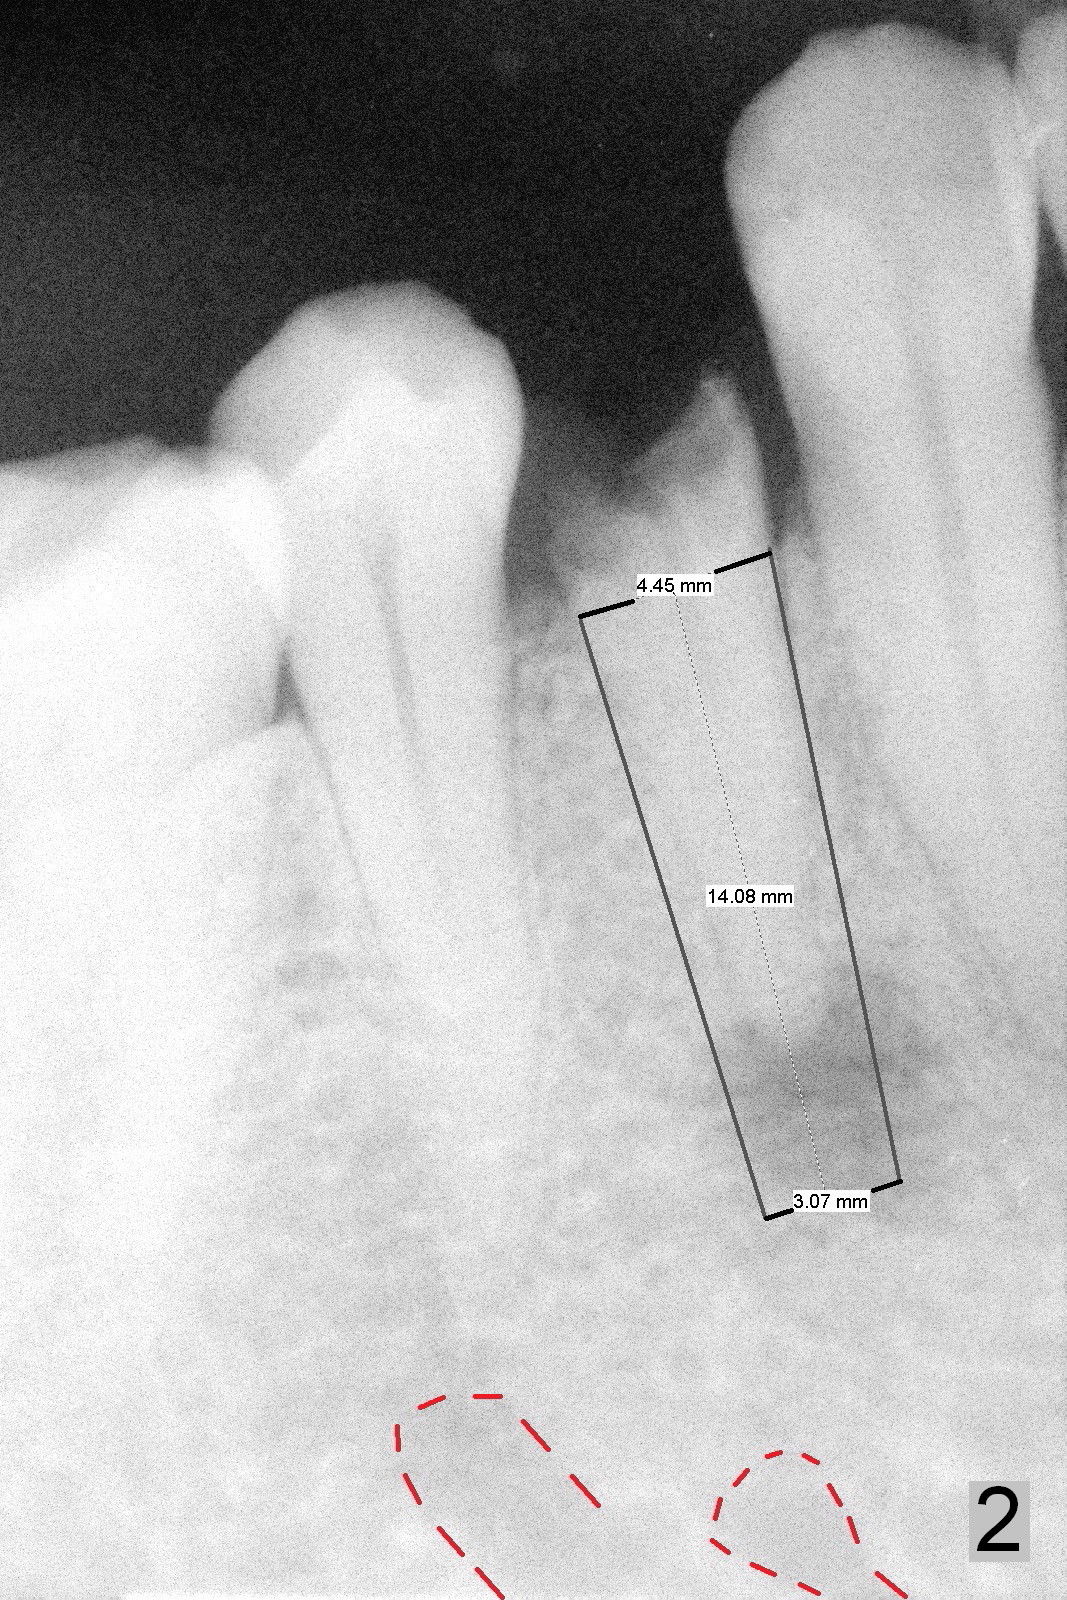

A 54-year-old man develops acute apical periodontitis associated with the tooth #28 (Fig.1). The latter appears to be non-salvageable with large periapical radiolucency (*). A 4.5x14 mm bone-level implant will be placed (Fig.2). The depth of osteotomy is to be tightly controlled after extraction (Fig.3 red long arrow) to avoid damage to the possible double Mental Loops (Fig.2 red dashed lines, 17 mm from the gingival margin). If the insertion torque is high, an immediate provisional is going to be fabricated. Bone graft is expected.